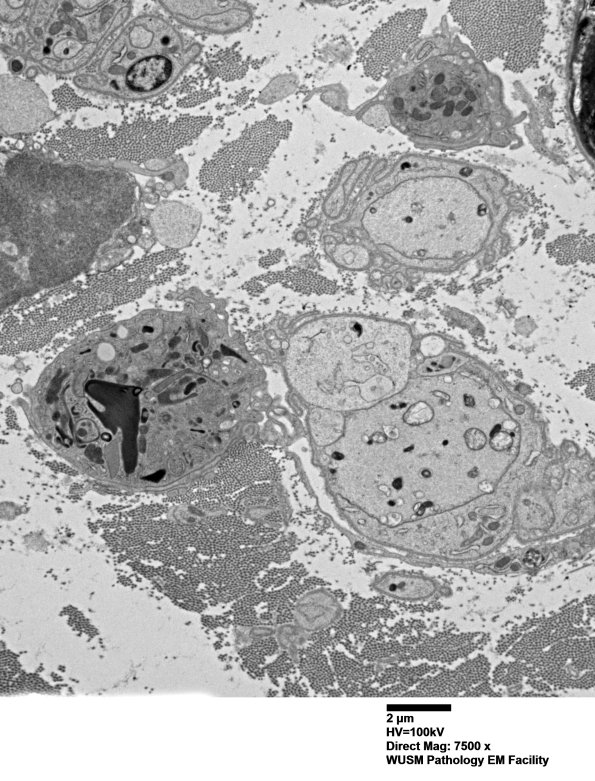

4F6,7 There are two adjacent processes, one an axon and the second a pale Schwann process (arrow) with endoplasmic reticulum and a few smudged ribosomes. (electron micrographs)